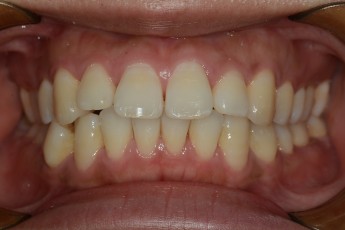

BEFORE & AFTER